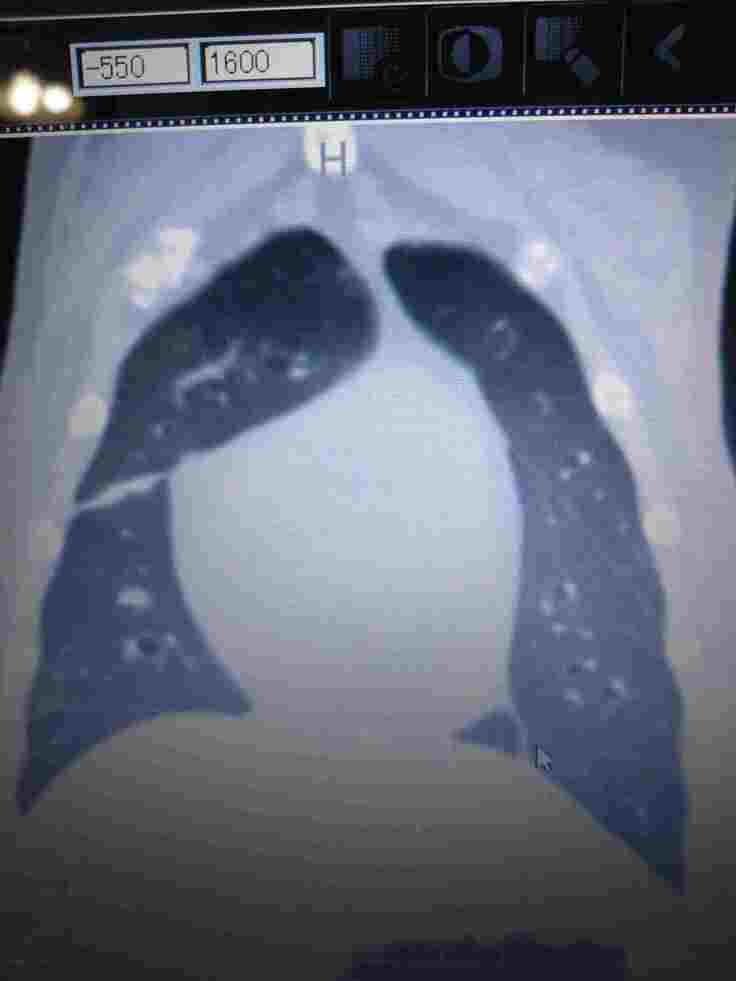

CT検査画像

パグのジョー(15歳)が悪性黒色腫(ステージ4)を発症し、進行のとても早いガンで既に肺に転移している状態で、手術はもう出来ない状態だと言われました。数年前から後両足が弱り現在は自力での歩行はできません、膀胱炎や急性肝炎など入退院を繰り返しようやく最近では体調が少し安定してきたかなと思った矢先に、御飯が左側の口からよくこぼれるようになってなにげに顎の下を触ると少し腫れているのに気づき、すぐに病院で診察してもらいましたが、詳しい検査をしないと分からないとのことで、腫瘍専門がある病院を紹介してもらい、造影剤を使用したCT検査、組織検査の結果、口腔悪性黒色と診断され腫瘍の大きさや肺に迄転移していることから手術は出来ないとのことで放射線治療しか有効な治療はないと言われました。ガンの進行が早く、何も治療をしないと口腔が壊死していく可能性があると説明され、根治は困難ですが、せめて最後迄御飯を食べてもらいたいと思い、放射線治療をしてあげたいと思いました。しかし、高額の検査費と治療費の為、放射線治療するのはかなり困難と半ば諦めていた時に、この活動を知り、せめてもう少しでもジョーとの時間を過ごせるように、皆様のご支援よろしくお願いいたします。

CT検査(造影剤)

今までの検査費(CT)1回 ¥111,760